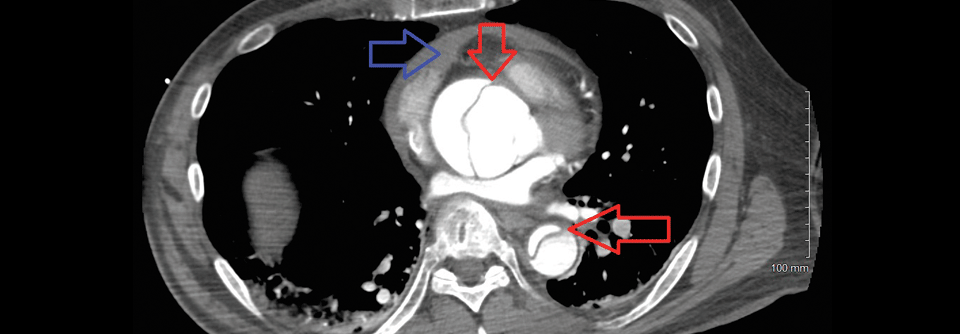

Nicht immer treten die für eine Aortendissektion typischen Zeichen auf. 1: Aorta descendens mit Dissektion. 2: Aortenisthmus. Nicht immer treten die für eine Aortendissektion typischen Zeichen auf. 1: Aorta descendens mit Dissektion. 2: Aortenisthmus. © wikimedia/Dr. Lars Grenacher (CC BY-SA 3.0)

Bei der 57-jährigen Patientin sprach eigentlich alles für ein neurologisches Problem. Während der Physiotherapie war sie mit tonisch-klonischen Krämpfen zusammengeklappt. Der Anfall hatte sich auch im Krankenwagen fortgesetzt. Im Krankenhaus angekommen fiel neben einer rigiden Hyperflexion im Ellbogengelenk und der Hyperextension der linken Hüfte vor allem der niedrige Blutdruck ins Auge, berichten die Herzchirurgin Dr. Rachel Eikelboom und ihr Kollege von der…